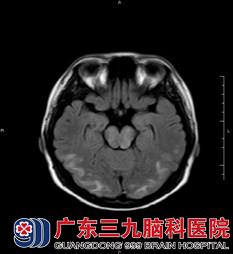

陈小姐在外院检查的MR提示颅内多发异常信号,神经内二科的医生主任结合其临床症状,考虑为子痫性脑病,不排除桥脑中央髓鞘溶解综合症;诊断初步考虑是可逆性脑后部白质病变? 静脉窦血栓形成?。陈小姐进一步完善了MR+增强+MRV检查,结果提示:1、双侧额顶枕叶、桥脑及中脑、左侧小脑半球、双侧基底节区及右侧侧脑室旁,左侧放射冠区多发病变。结合其病史,医生考虑为可逆性后部白质脑病综合症,建议治疗后复查;2、MRV检查示未见异常。

该病与高血压脑病,先兆子痫/子痫,急性肾小球肾炎,肾衰竭,系统性红斑狼疮等疾病相关。目前认为主要是颅内高灌注、血管内皮损伤及交感神经调节异常所致,通常表现为头痛(弥漫性钝痛,持续进展)、癫痫发作(双侧枕叶尖波的癫痫持续状态),意识障碍及视觉障碍四联征。其具有累及大脑后部白质的双侧对称的特征性影像学改变,这种改变在MR的T2压水像上最为明显(图1、图2),另外其病灶在MR弥散成像上的高ADC信号(图3)也可以与其他疾病相鉴别。